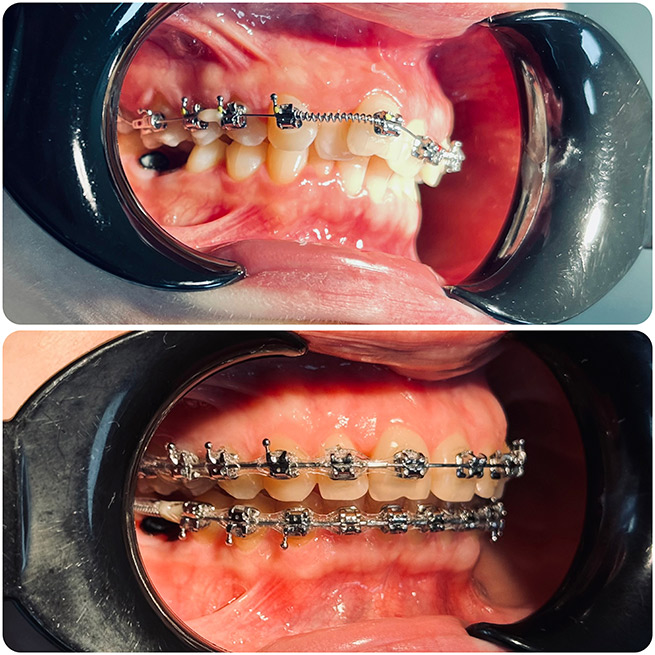

Брекет-системи – класичне та ефективне рішення для виправлення прикусу та вирівнювання зубів. Я працюю з:

- Металевими брекетами (надійні та доступні);

- Самолігуючими брекетами (металеві та керамічні);